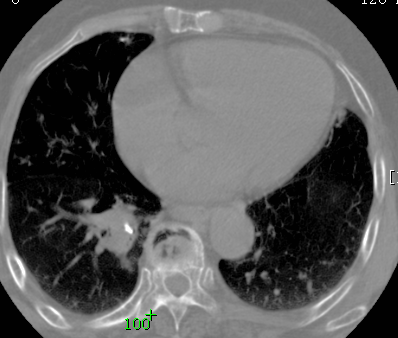

标题: CT26680:肺部右下肺静脉干结节的界定 [打印本页]

标题: CT26680:肺部右下肺静脉干结节的界定

经追查说有支扩咯血病史,但不确定

考虑1、周围型肺癌,2肺静脉畸形,前者可能大,建议增强检查。

考虑1、周围型肺癌,2肺静脉畸形,前者可能大,建议增强检查。支持!

不排除右肺下叶周围型肺癌可能。

中心型肺癌,纤支镜可帮助明确。